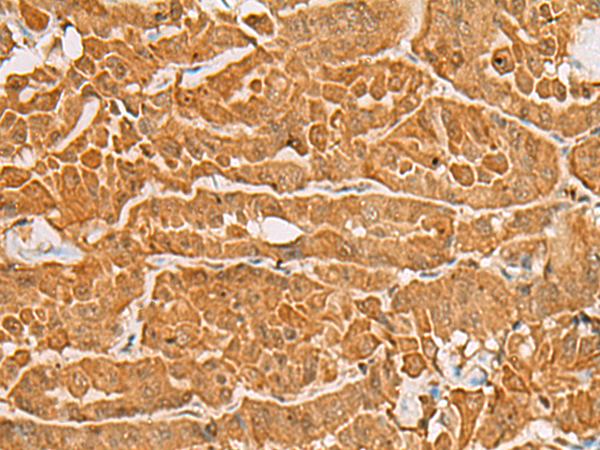

分类: 科研抗体货号: P07528别名: ALG-2, PEF1B应用: WB,IHC反应种属: Human, Mouse